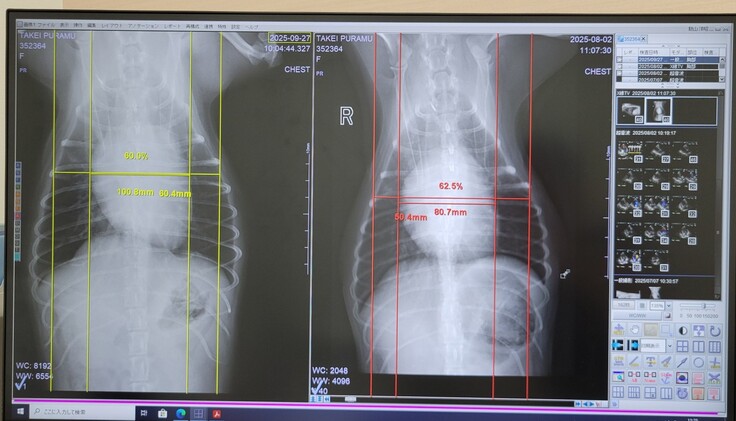

以下2枚のレントゲン写真でも、心臓肥大化しておらず安心しました。

唯一、エコー検査の結果でe波と呼ばれる数値が高かったため、ここを抑える処方として、少し利尿剤を増やすこととはなりましたが、術前の量に比べるとまだまだ少なく、数値的にも負担はなさそうなので、早め早めの対応をすることとしました。